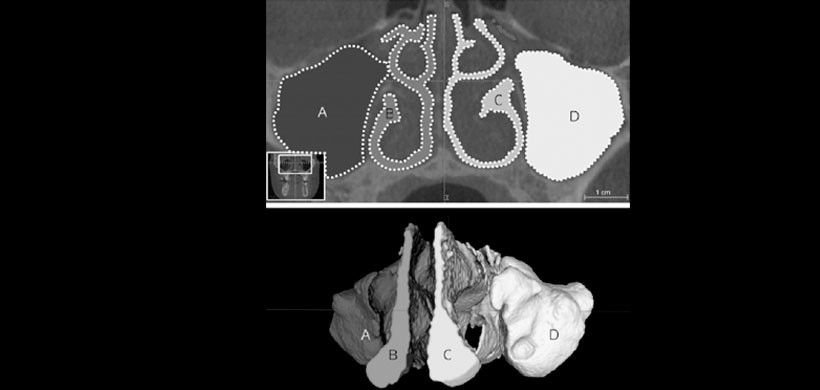

Fig 1. CBCT, en el cual se muestra la selección del área de interés a determinar el volumen del espacio aéreo de las fosa nasal derecho, se aprecia que existen parámetros a tener en cuenta, la línea media sagital, el paladar duro, el área tiene que ser visualizado de manera sagital y de manera frontal para poder tener la cobertura total.

Fig 2. CBCT, determinación de los volúmenes del espacio aéreo de las fosas nasales, posteriormente se realiza una diferencia de lados y se determina la discrepancia para ver el grado de severidad de la desviación del tabique nasal.